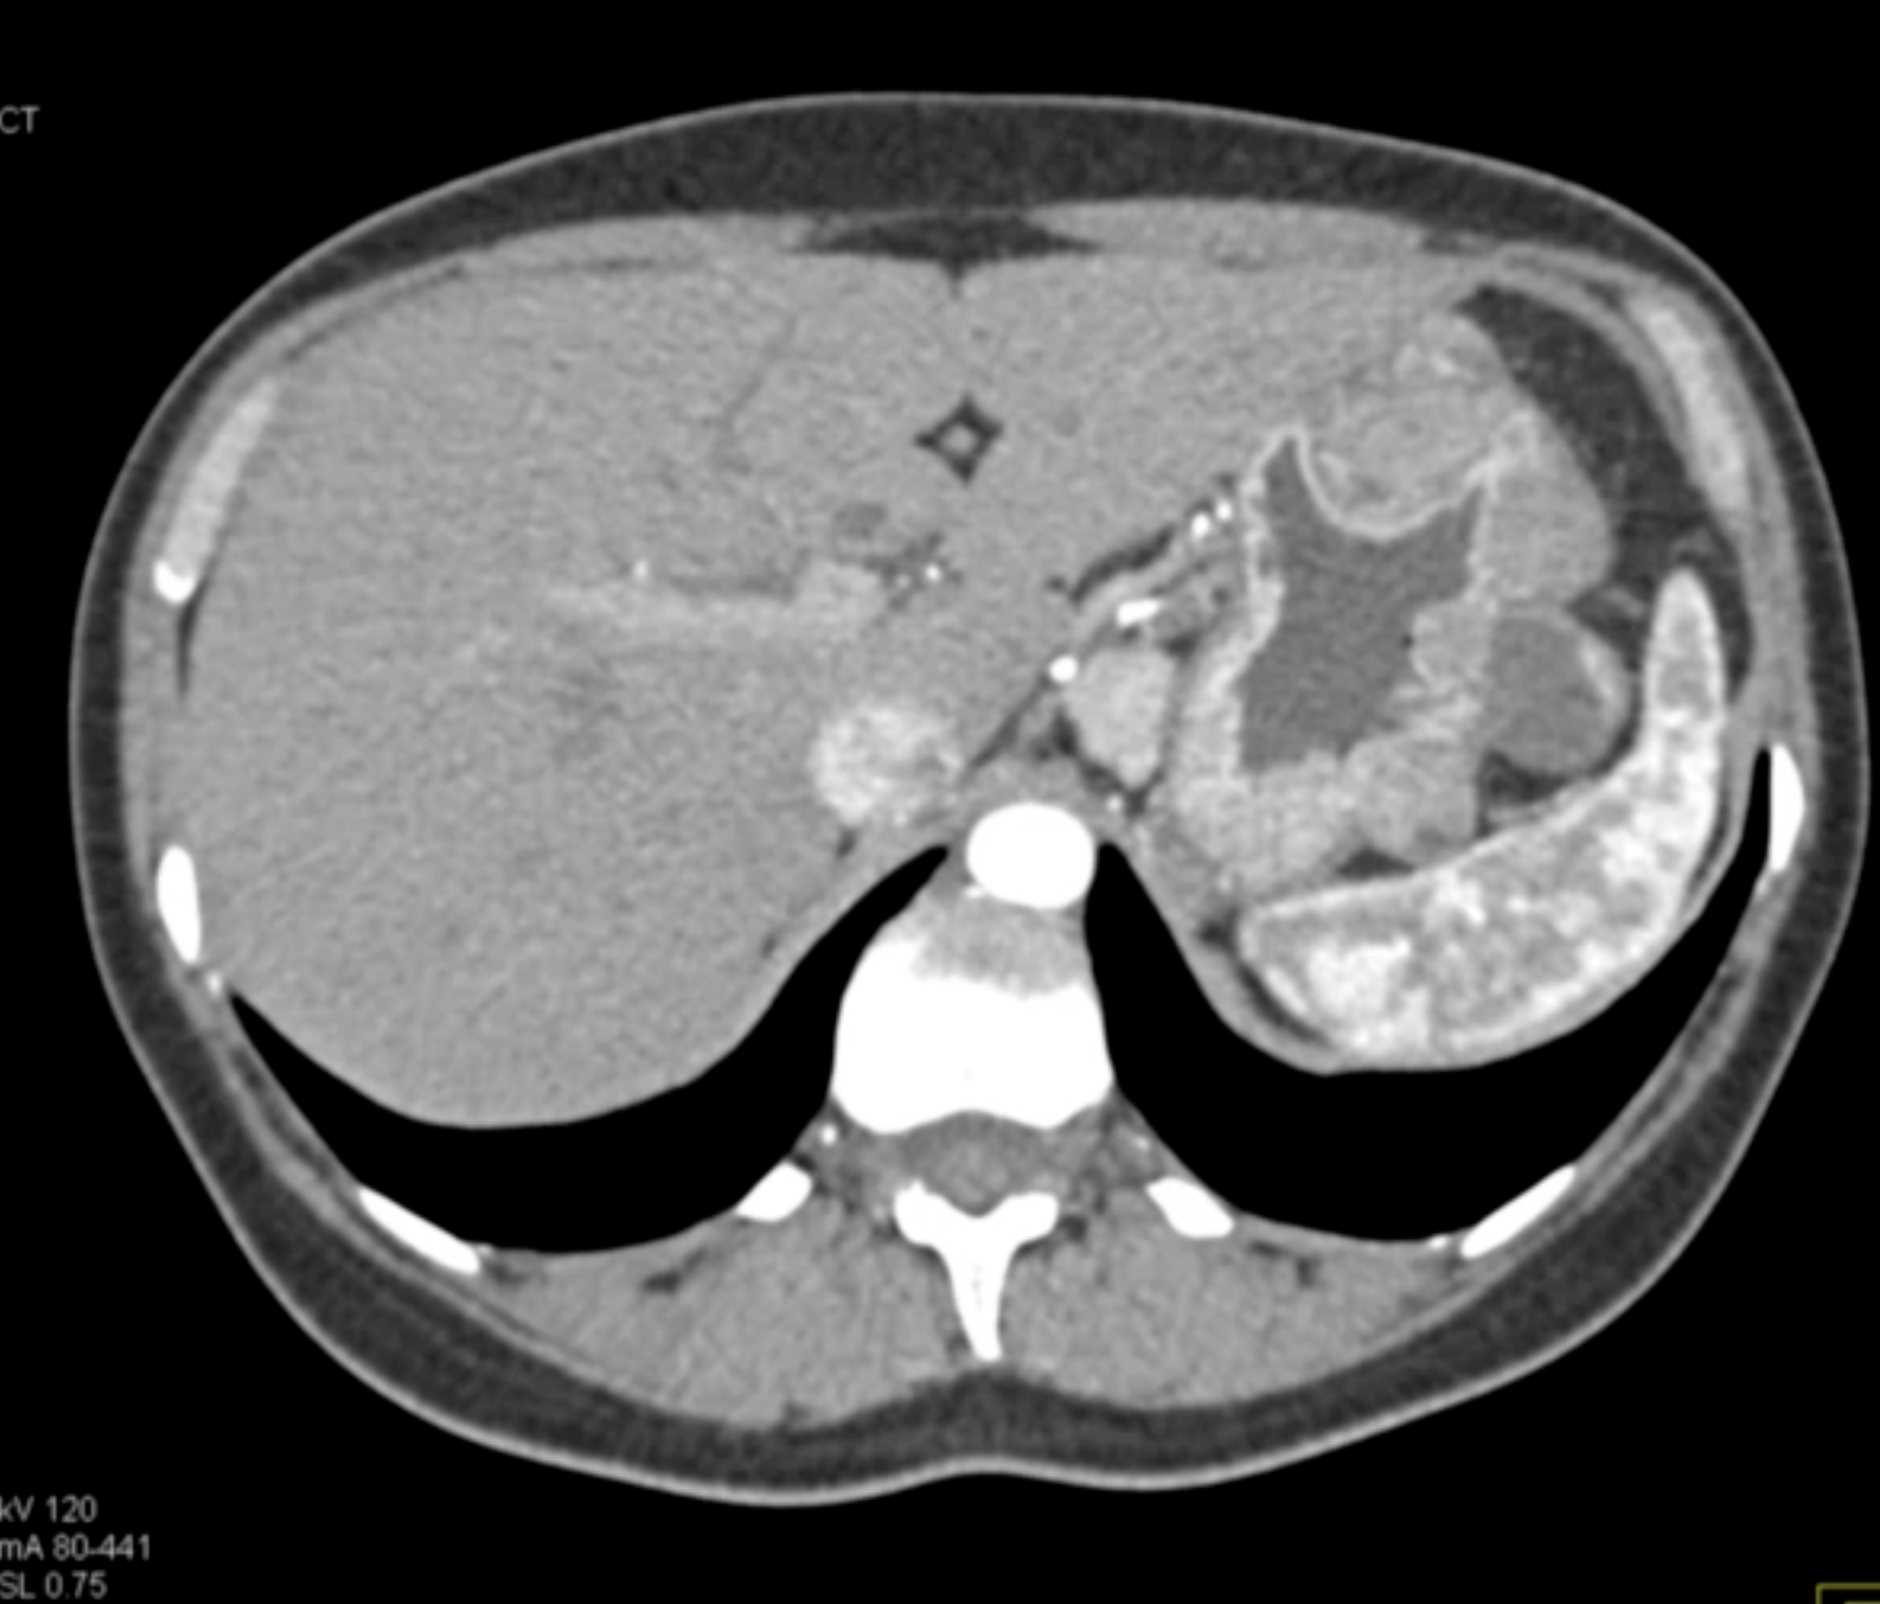

Multiple Gastric GIST Tumors with Spread to Nodes (Carney-Stratakis Syndrome)